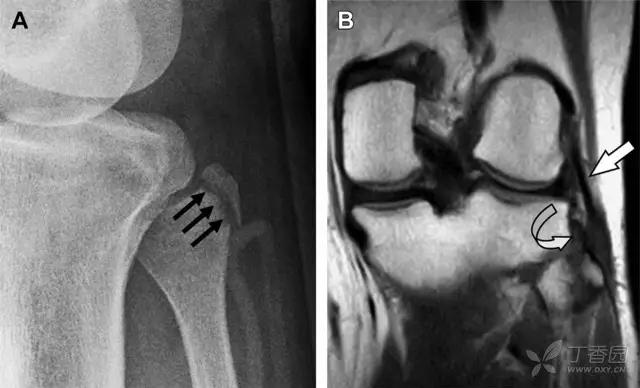

15 腓骨头撕脱性骨折

膝关节外侧由髂胫束、股二头肌和肌腱、外侧关节囊韧带及外侧副韧带组成。外侧副韧带对抗过度内旋*力暴**,维持膝关节稳定。当内旋*力暴**足够大时,韧带断裂或腓骨头撕脱性骨折就发生了。在 X 线片上,骨折线垂直于股骨头外侧(图 8)。

图 8 过度伸展引起的腓骨头撕脱性骨折

A 侧位片示腓骨头外侧的垂直骨折(箭头)。B MRI 冠状位 T1 加权像示骨折碎片同时附着于外侧副韧带(箭头)和弓状韧带上(弧形箭头)。